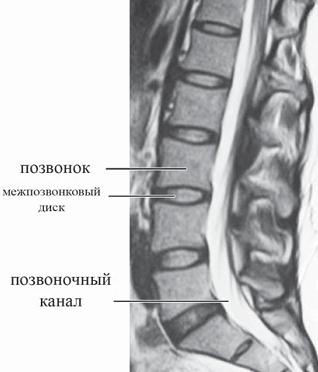

![]() Фото № 1. Макет, шейного отдела позвоночника человека, на котором хорошо видно, как позвоночная артерия проходит через отверстия в поперечных отростках, образующих таким образом костный канал для позвоночной артерии. Есть в шейном отделе позвоночника и свои «оперуполномоченные» — суставные отростки, которые принимают участие в формировании дугоотростчатых суставов. А поскольку суставные поверхности на этих отростках расположены ближе к горизонтальной плоскости, то в совокупности это значительно расширяет возможности шейного отдела позвоночника, обеспечивает более эффективную подвижность головы, позволяет достигать большего угла скручивания. Однако последнее как раз и стало уязвимым местом для шейного отдела, учитывая небольшую прочность шейных позвонков, их вес и степень подвижности. Как говорится, даже у «особого отдела» есть своя «ахиллесова пята». Обнаружить же, где именно заканчиваются пределы вашего «особого отдела», вы можете по седьмому шейному позвонку. Дело в том, что длина остистых отростков (кстати, концы их раздвоены, кроме VII) увеличивается от II к VII позвонку. Остистый отросток седьмого шейного позвонка самый длинный и к тому же утолщён на конце. Он является весьма заметным анатомическим ориентиром: при наклоне головы на задней поверхности шеи хорошо прощупывается верхушка наиболее выступающего остистого отростка. Кстати, данный позвонок так и называется по-латыни vertebra prominens — позвонок выступающий. Это и есть та самая легендарная «семёрка», благодаря которой можно сосчитать ваши позвонки с диагностической точностью. Грудной отдел позвоночника состоит из 12 позвонков. Латинское название vertebrae thoracicae — позвонки грудные. Латинское слово thorax — грудная клетка — образовано от греческого слова thoraks — грудь. В медицинских документах позвонки грудного отдела обозначаются как «ТЬ> или «Т». Высота тел данных позвонков постепенно возрастает от I до XII позвонка. Остистые отростки накладываются друг на друга черепицеобразно, прикрывая дуги нижележащих позвонков. МРТ № 2 ![]() На МРТ № 2 — грудной отдел в состоянии «норма» Грудной отдел должен иметь нормальную степень кифоза (угол кифоза по Stagnara формируется линией, параллельной замыкательным пластинкам ТIII и ТXI= 25°). Позвоночный канал на грудном уровне имеет округлую форму, что делает эпидуральное пространство узким почти по всей окружности дурального мешка (0,2–0,4 см), а на участке между TVI и ТIX он наиболее узок. Сагиттальный размер: ТI-ТХI = 13–14 мм, ТXII = 15 мм. Поперечный диаметр: > 20–21 мм. Высота межпозвонковых дисков: самая меньшая на уровне ТI, на уровне ТVI-ТХI приблизительно 4-5 мм, наибольшая на уровне ТХI-ТХII. Также характерным признаком для большинства грудных позвонков является наличие на боковых поверхностях тел верхней и нижней рёберных ямок для сочленения с головками рёбер, а также наличие рёберной ямки на поперечных отростках для соединения с бугорком ребра. Из-за специфики своей конструкции, небольшой высоты межпозвонковых дисков этот отдел, безусловно, не столь подвижен, как шейный отдел. Однако и предназначен он для других целей. Позвонки грудного отдела в совокупности с грудными рёбрами, грудиной образуют костную основу верхней части туловища — грудную клетку, которая является опорой для плечевого пояса, вместилищем жизненно важных органов. Она позволяет использовать межрёберную мускулатуру при дыхательных движениях. Соединение грудных позвонков с рёбрами придаёт этому отделу позвоночника большую жёсткость благодаря рёберному каркасу грудной клетки. Так что эти позвонки можно образно сравнить с людьми, слаженно и эффективно работающими в одной большой команде, чётко исполняющими свои функции и обязанности. ![]() Рисунок № 11. Грудной позвонок. Вид сверху 1 — дуга позвонка; 2 — остистый отросток; 3 — поперечный отросток; 4 — рёберная ямка поперечного отростка; 5 — позвоночное отверстие; 6 — верхний суставной отросток; 7 — верхняя рёберная ямка; 8 — тело позвонка Поясничный отдел позвоночника составляют 5 самых крупных позвонков, имеющих массивные, бобовидной формы тела позвонков, прочные отростки. Высота и ширина тел позвонков постепенно увеличиваются от первого до пятого позвонка. Латинское название vertebrae lumbales — позвонки поясничные, лат. lumbalis — поясница. Соответственно обозначаются: первый поясничный позвонок — Lp второй поясничный позвонок — LII и так далее. Подвижный поясничный отдел позвоночника соединяет малоподвижный грудной отдел с неподвижным крестцом. Это самые настоящие «трудяги», которые мало того, что испытывают значительное давление со стороны верхней части тела, так ещё и по жизни подвергаются серьёзной дополнительной нагрузке, о которой было частично сказано в предыдущей главе. МРТ № 3

На МРТ № 3 — поясничный отдел позвоночника. (На данном «контрольном» снимке наблюдаются остаточные явления дегенеративно-дистрофического процесса в сегменте LV-SI после устранения методом вертеброревитологии секвестрированной грыжи межпозвонкового диска.) В поясничном отделе форма позвоночного канала, создаваемая телом и дужками позвонка, вариабельна, но чаще она пятиугольная. В норме позвоночный канал в пояснично-крестцовом отделе сужен в переднезаднем диаметре на уровне LIII и LIV позвонков. Его диаметр каудально увеличивается, и поперечное сечение канала приобретает форму, близкую к треугольной, на уровне LV-SI. У женщин канал имеет тенденцию к расширению в нижней части крестцовой области. Сагиттальный диаметр значительно уменьшается от LI к LIII почти неизменен от LIII к LIV и увеличивается от LIV к LV. В норме переднезадний диаметр позвоночного канала в среднем равен 21 мм (15–25 мм). Существует простая и удобная формула определения ширины позвоночного канала: нормальный сагиттальный размер не менее 15 мм; 11–15 мм — относительный стеноз; менее 10 мм — абсолютный стеноз. Уменьшение этого соотношения свидетельствует о сужении канала. Высота поясничных межпозвонковых дисков 8-12 мм, нарастает от LI до LIV-LV, обычно уменьшается на уровне LV-SI |